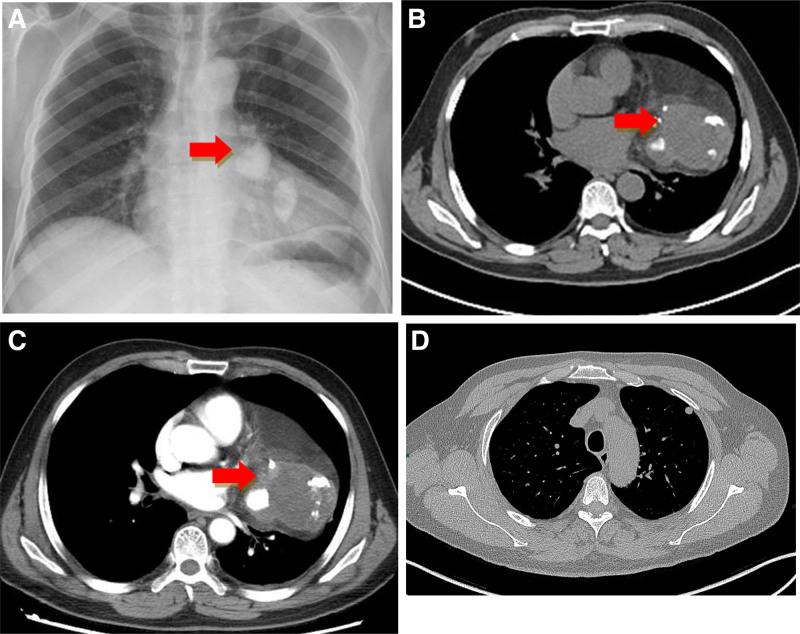

A 51-year-old man was admitted with cough and sputum accompanied by fever. X-ray and CT showed a bulky anterior mediastinal mass that was initially misdiagnosed as a teratoma. PET/CT demonstrated a lesion on that location showing a small area of moderately intense uptake. After surgical excision, histopathological examination via hematoxylin and eosin first revealed the diagnosis of malignant undifferentiated tumors. The results of immunohistochemical evaluations were as follows: P63 (scattered +), VIMENTIN (giant cell +), CD68 (KPI; giant cell +), SMA (-), and Ki-67 (Li: 50%). Molecular pathology: MDM2 gene status (+) with amplification.

一名51岁男性因咳嗽、咳痰伴发热入院。X线和CT显示前纵隔有一个巨大肿块,最初被误诊为畸胎瘤。PET/CT显示该部位有一个病变,有一小片区域摄取中等强度放射性。手术切除后,苏木精-伊红染色的组织病理学检查最初显示为恶性未分化肿瘤。免疫组化评估结果如下:P63(散在阳性)、波形蛋白(巨细胞阳性)、CD68(KPI;巨细胞阳性)、平滑肌肌动蛋白(阴性)和Ki-67(Li:50%)。分子病理学:MDM2基因状态为阳性且有扩增。